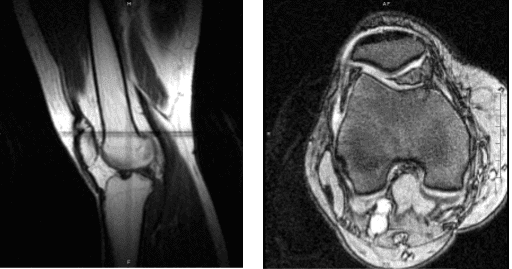

The patient 43 year-old male presents with right knee pain since the car accident. He has tried PT, chiro, NSAIDs with no relief. He is back to work as conductor at LIRR. Pain was localized to the medial tibiofemoral joint line. The patient was treated conservatively for pain, but had failed.

We did an MRI, which showed a tear of the medial meniscus of the right knee. We discussed treatment options and opted for surgical management.

Magnetic resonance imaging of the right knee